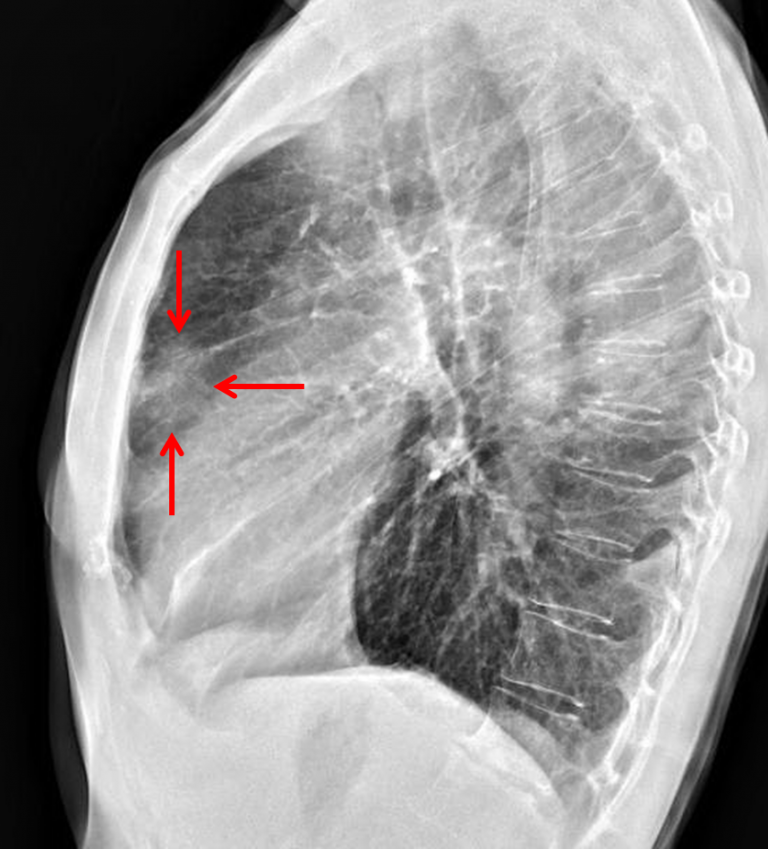

Age: 57

Sex: Female

Indication: Cough, dyspnea

Sample ReportNodular density projecting in the anterior mediastinum on the lateral projection, concerning for an anterior mediastinal mass. Recommend chest CT for further evaluation.

Large lung volumes, which may relate to obstructive pulmonary disease. No evidence of pneumonia.